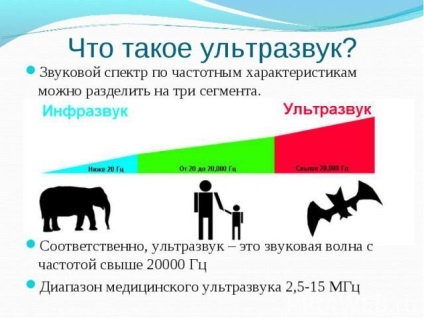

Ultrasunete se realizează cu ajutorul undelor ultrasonice care funcționează la frecvențe foarte joase. La ecografie, nu este absolut nimic de-a face cu unda de raze X, care este iradiat de radiație a corpului (chiar dacă într-o cantitate foarte mică). Și pentru că ultrasunete se poate face destul de siguranță la femeile gravide. Aceste date, care sunt primite de către un specialist în cadrul procedurii, acestea sunt foarte informativ, în comparație cu raze X. Intr-un studiu al fătului și organele pelvine femeile pot fi considerate „viu“ pentru o lungă perioadă de timp, din unghiuri diferite și din poziții diferite.

Acest lucru este tot ceea ce nu se poate face cu o fotografie simplu aparat de raze X. De aceea, ne mult mai ușor, mai plăcută și mai sigură. Acesta poate fi folosit pentru a detecta orice anomalii la fat in curs de dezvoltare, sau de a descoperi multe anomalii confirmă corectitudinea și respectarea termenelor limită. Răspunsul la întrebarea dacă ultrasunete este sigur, este baza numelui său. Este toate aceleasi vibratii, dar numai pentru acele frecvențe care prinde urechea persoana medie nu se poate. Acesta este sunetul, care este larg răspândită în natură, în lumea animală. Pur și simplu este organism viu nu este disponibil mai mare pe această planetă. Numele lui a doua - supersonice. frecvența normală de oscilație este de 3,5 la 5 MHz. Este pe baza faptului că aceste fluctuații pentru a prinde fără un dispozitiv special, nu este posibil, și a existat o credință că SUA - este destul de dăunătoare și fă-o în timpul sarcinii este imposibil. De ce auzim sunetele? Orice fluctuații în aer sunt obstacolele în calea sa, de la care acestea sunt reflectate, se resping reciproc, care creează zgomotul captat de urechile noastre.